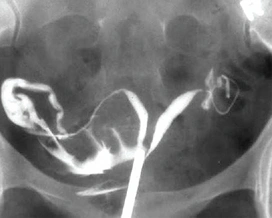

• 쌍각자궁의 모습 :

쌍각 자궁 사진